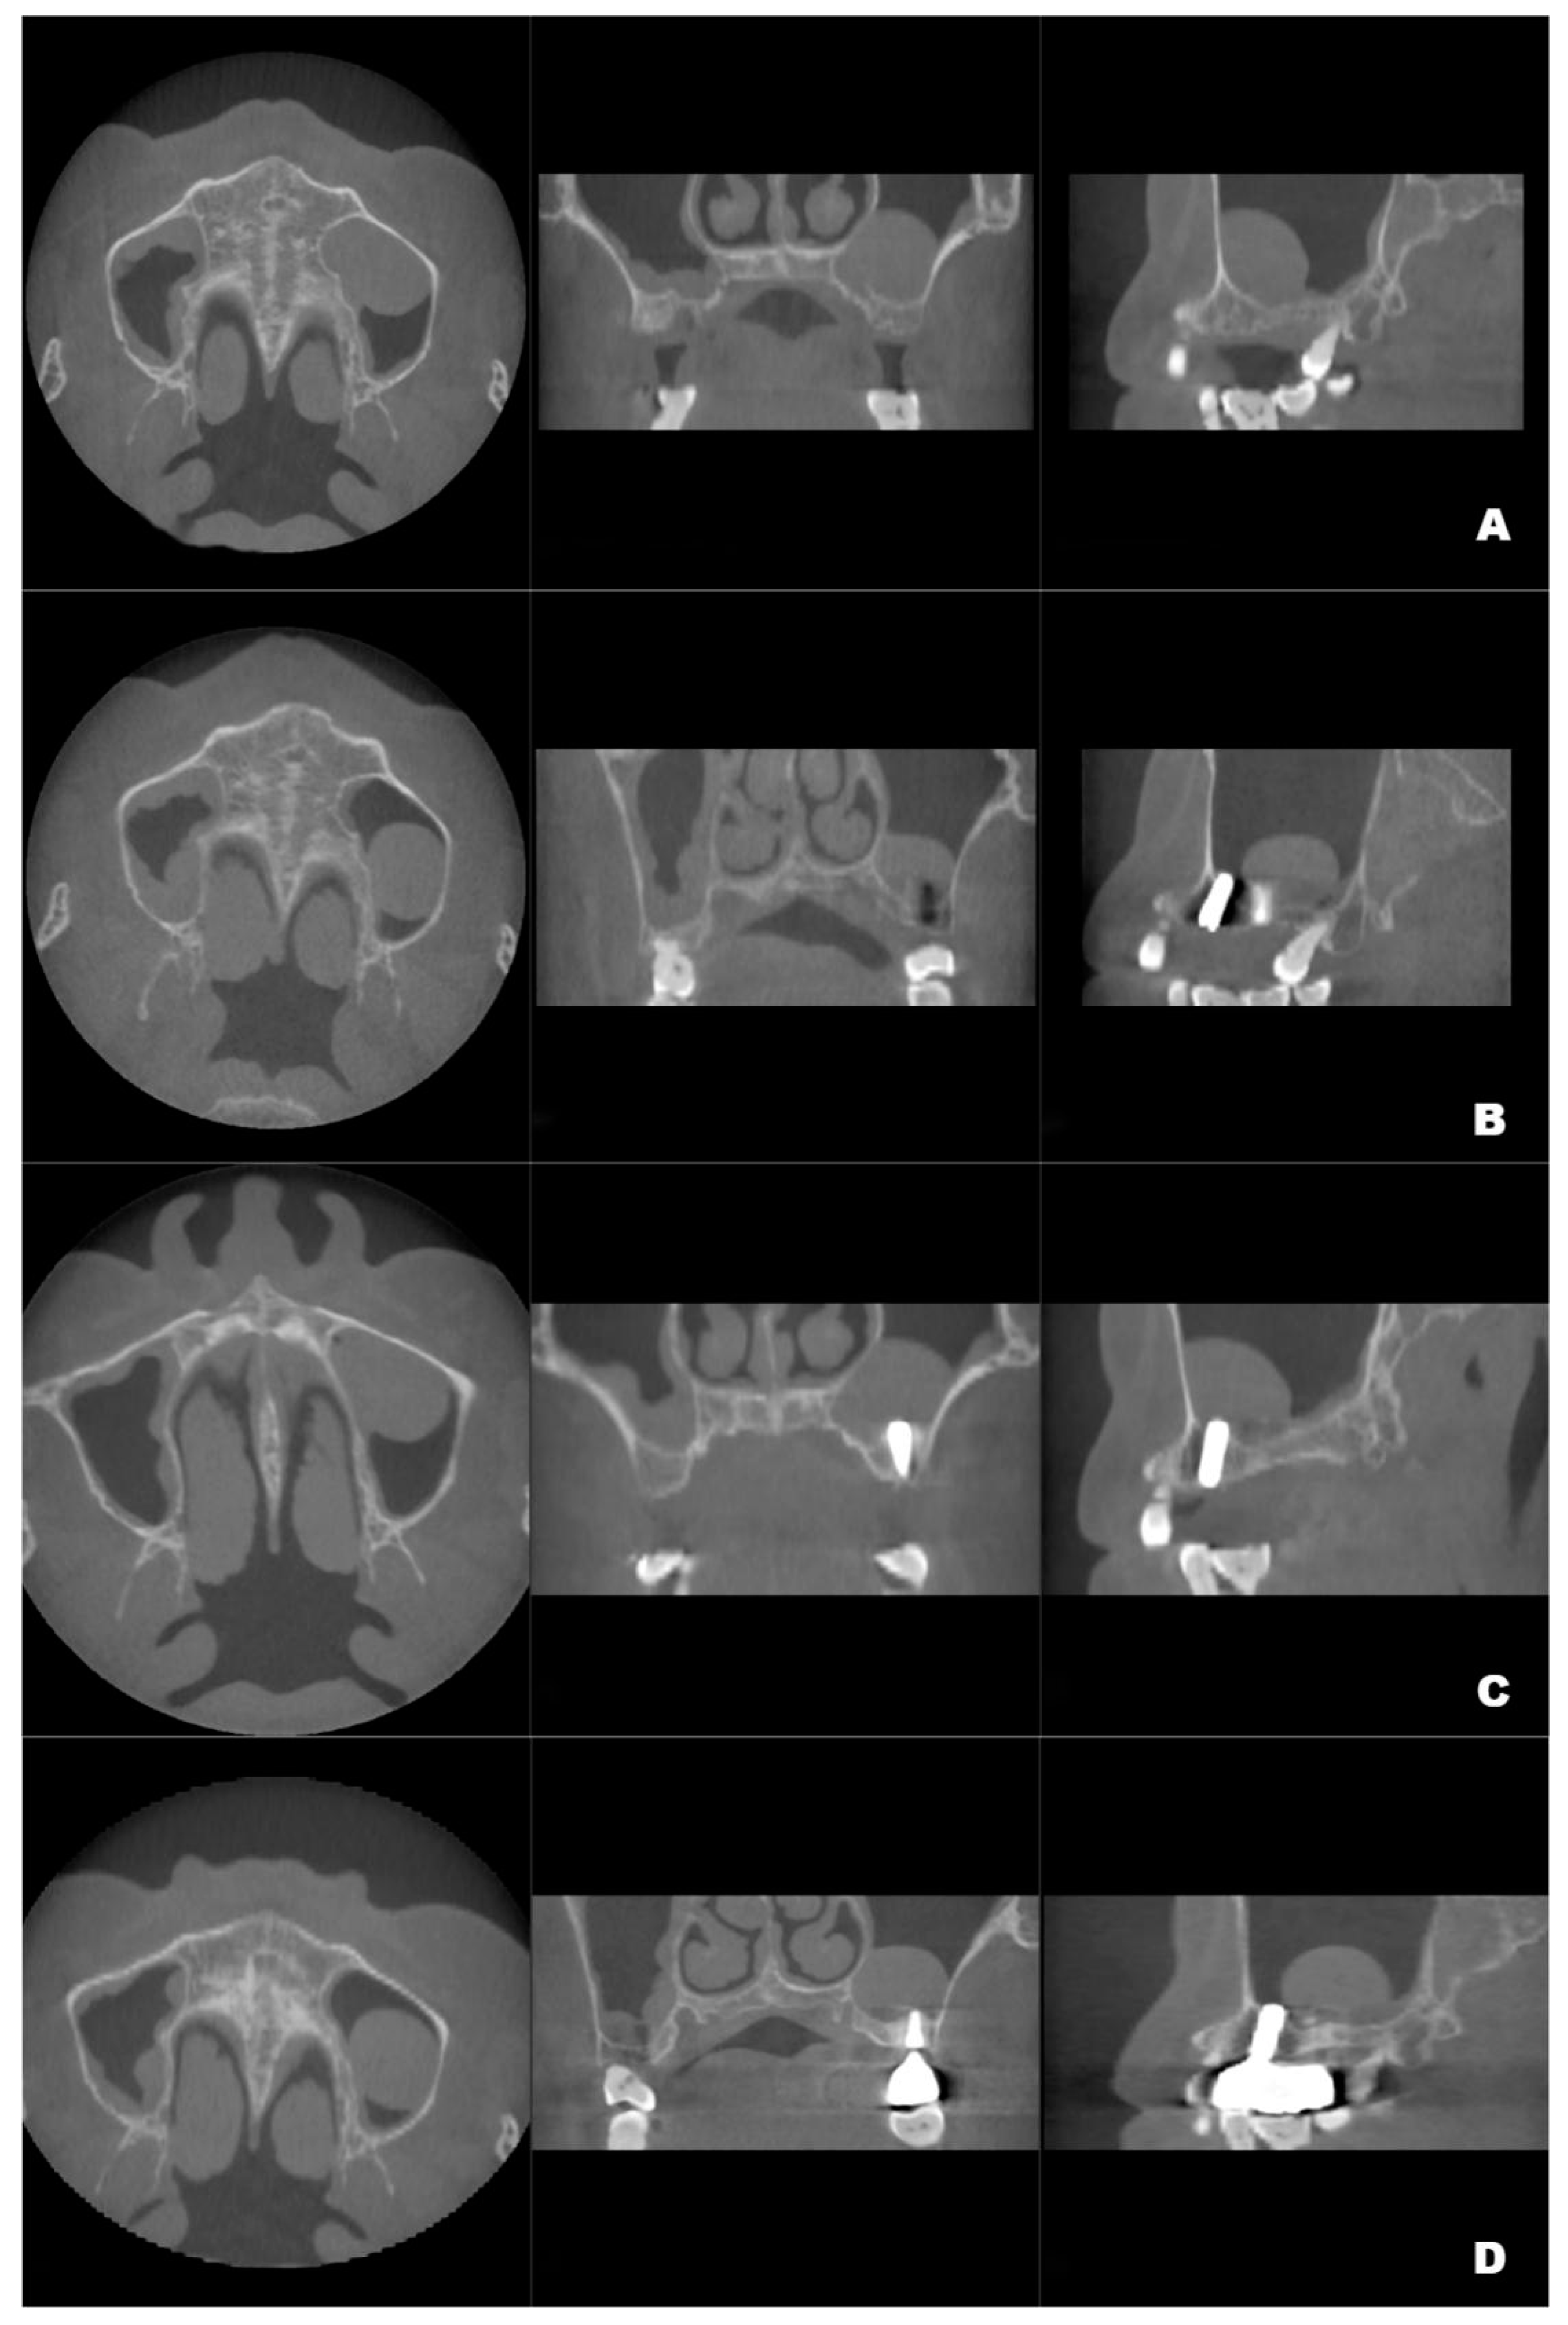

2. Case Report

2.2. Surgical Procedures and Postoperative Management

2.3. Postoperative Examinations